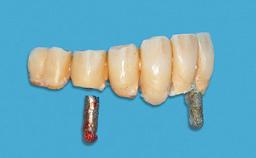

# of Implants 2

Type of Implants One-Piece

Attachment One-Piece

Prosthesis Type RDP

Defining Characteristics Fully edentulous lower jaw to be rehabilitated with an implant-borne removable overdenture